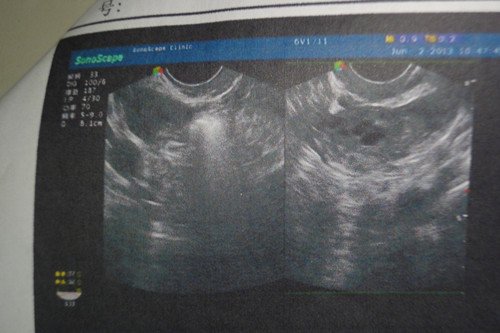

在三甲医院检查出慢性盆腔炎、细菌性阴道炎、宫颈糜烂中度,医生建议用Leep刀手术,我尚未生育

能不开刀 只用中药调理加上平时注意能治好么 望专家指点 最好能给个  中药处方。谢谢!一下是我的检查结果